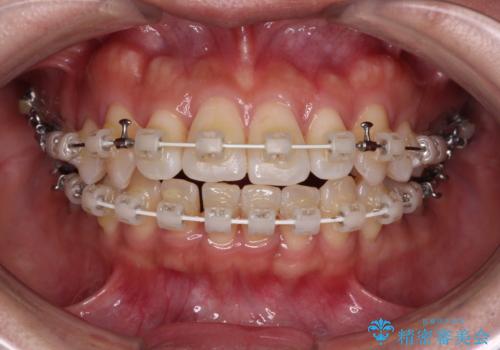

気になる八重歯 ワイヤー装置での非抜歯矯正

- 審美装置

- 上顎の八重歯と全体的なデコボコを気にして来院された患者様です。

口元の突出感はなかったため非抜歯矯正での対応となりますが、八重歯を改善する際に上顎前歯が前突する可能性があったため、上顎臼歯部にアンカースクリューを使用して、歯列が前方に転位しないようにすることとしました。

また舌のトレーニングを行うことで、上顎前歯の突出予防や上下前歯に隙間ができなくなるようにしました。